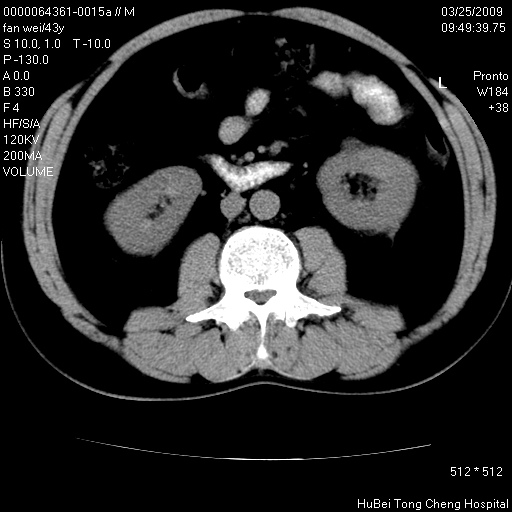

患者 男,43岁。左侧腰部不适两天。平素健康。无家族遗传病史。

腹部彩超提示:1)轻度脂肪肝。2)左肾多发囊性占位性病变;建议行进一步检查。

临床诊断:左肾多发囊性占位性病变,性质待定(多发肾囊肿?)。

双肾ct轴位平扫+增强扫描(层厚10mm,螺距1.0,重建间隔10mm),图像如下:

左肾体积变大,支持多囊肾。

双侧多囊肾!